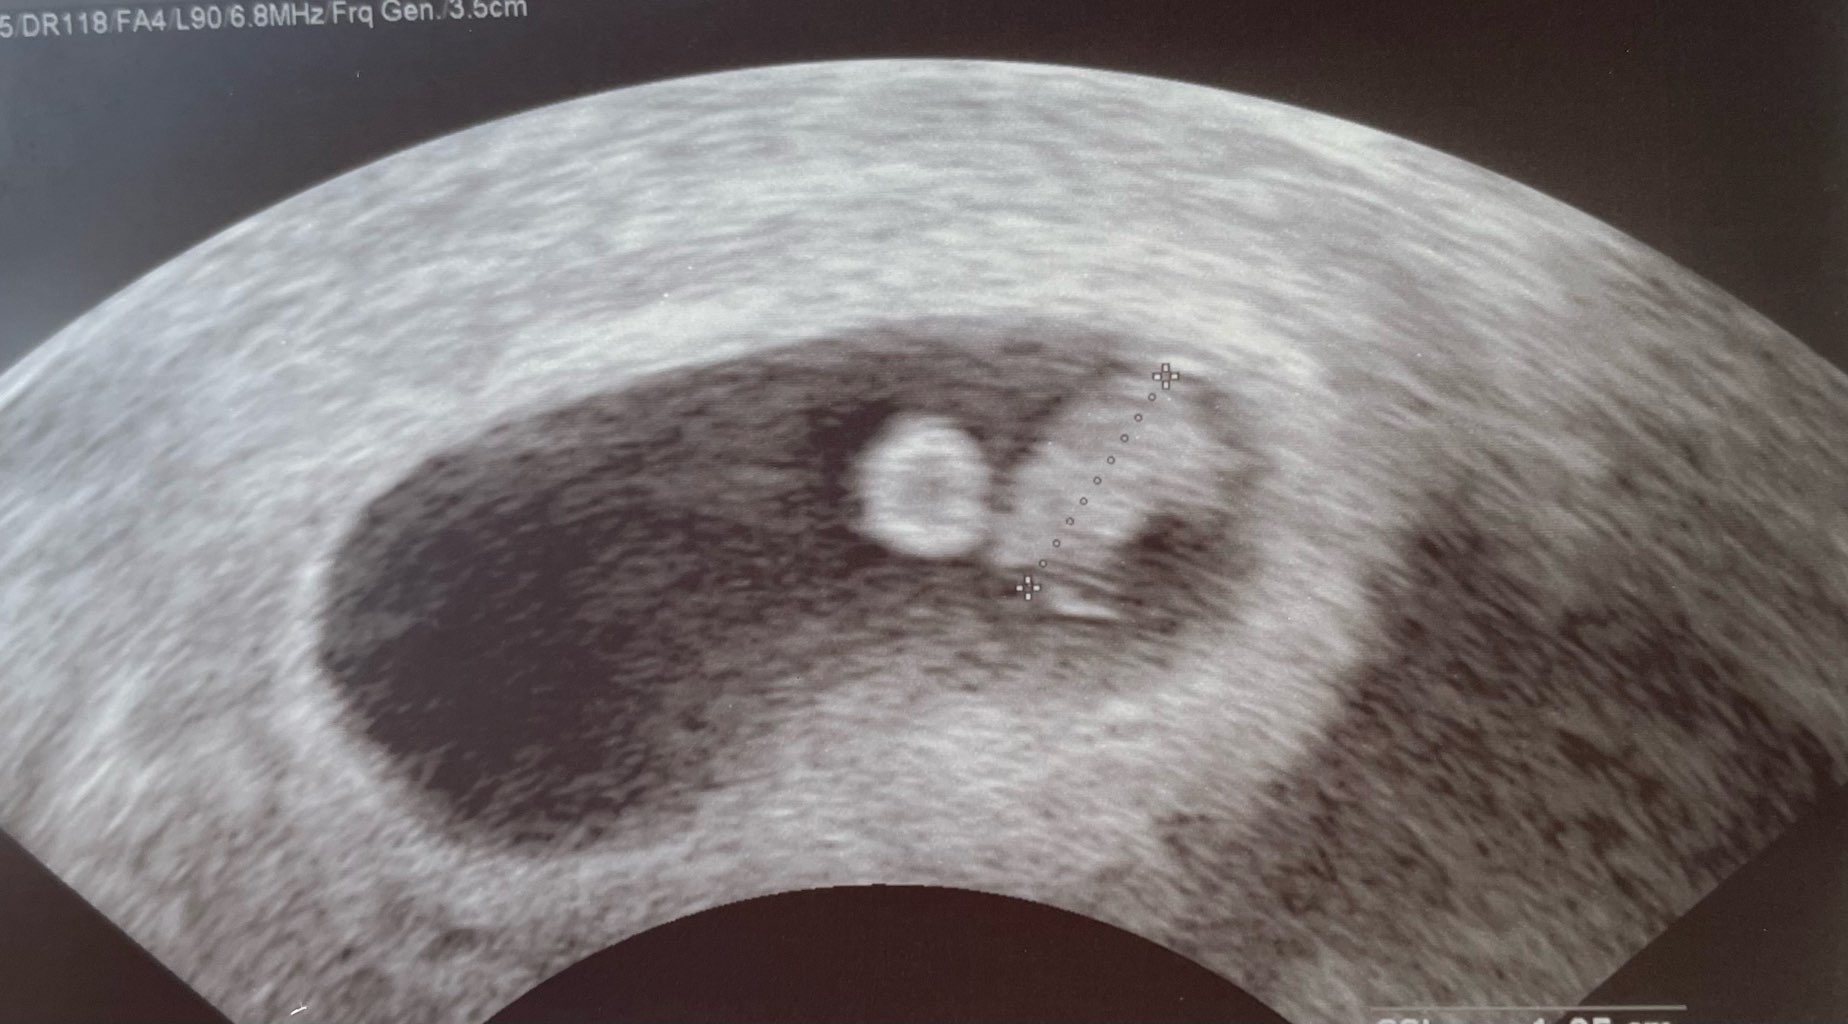

Dziewczyny! Mamy kolejnego dzidziusia! Serduszko boje, 1.05 cm. ♥️🥰 jestem zakochana po uszy🫶🏻 teraz modlić się i wierzyć ze wszystko dobrze się skończy 🤭 dziękuje za wszystkie kciuki 🙏🏻

Załączniki

• IMG_7852.jpeg

IMG_7852.jpeg

200,5 KB · Wyświetleń: 83